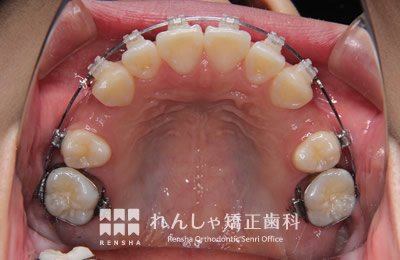

埋伏(まいふく)

永久歯が埋まったまま自然に萌出しないことがあります。周辺の歯に引っかかっていたり、歯胚(歯の卵)の位置や方向が悪い場合、分厚い歯ぐきに覆われている場合など様々です。埋伏している永久歯が隣接する永久歯の歯根を吸収してしまうこともあるので、引っ張り出す処置(牽引処置)が必要になることがほとんどです。場合によっては埋伏歯を抜歯してしまうこともあります。

他の永久歯に比べて生えてくるのが遅い場合(右上前歯は出たのに、左上は半年経っても出ない等)は注意が必要です。

右上5番目が埋まったままになっているため、スペースを作り引っ張り出しています。

治療前

| 主訴 | 前歯のがたつき |

|---|---|

| 診断名 | Angle Class II 上顎右側第二小臼歯の埋伏を伴う上顎前突 |

| 初診時年齢 | 10歳10か月 |

| 装置名 | マルチブラケット装置 |

| 抜歯非抜歯 | 非抜歯 |

| 治療期間 | 2年1か月 |

| 費用の目安 | 約41万円+消費税(検査料金、都度の処置費用等も合わせた総額) |

| リスク副作用 | 歯の移動に伴う軽微な歯根吸収、歯槽骨吸収、歯肉退縮(いずれも本症例ではほぼ無し)、矯正器具装着中のカリエスリスク増大(本症例ではカリエス発生無し) |